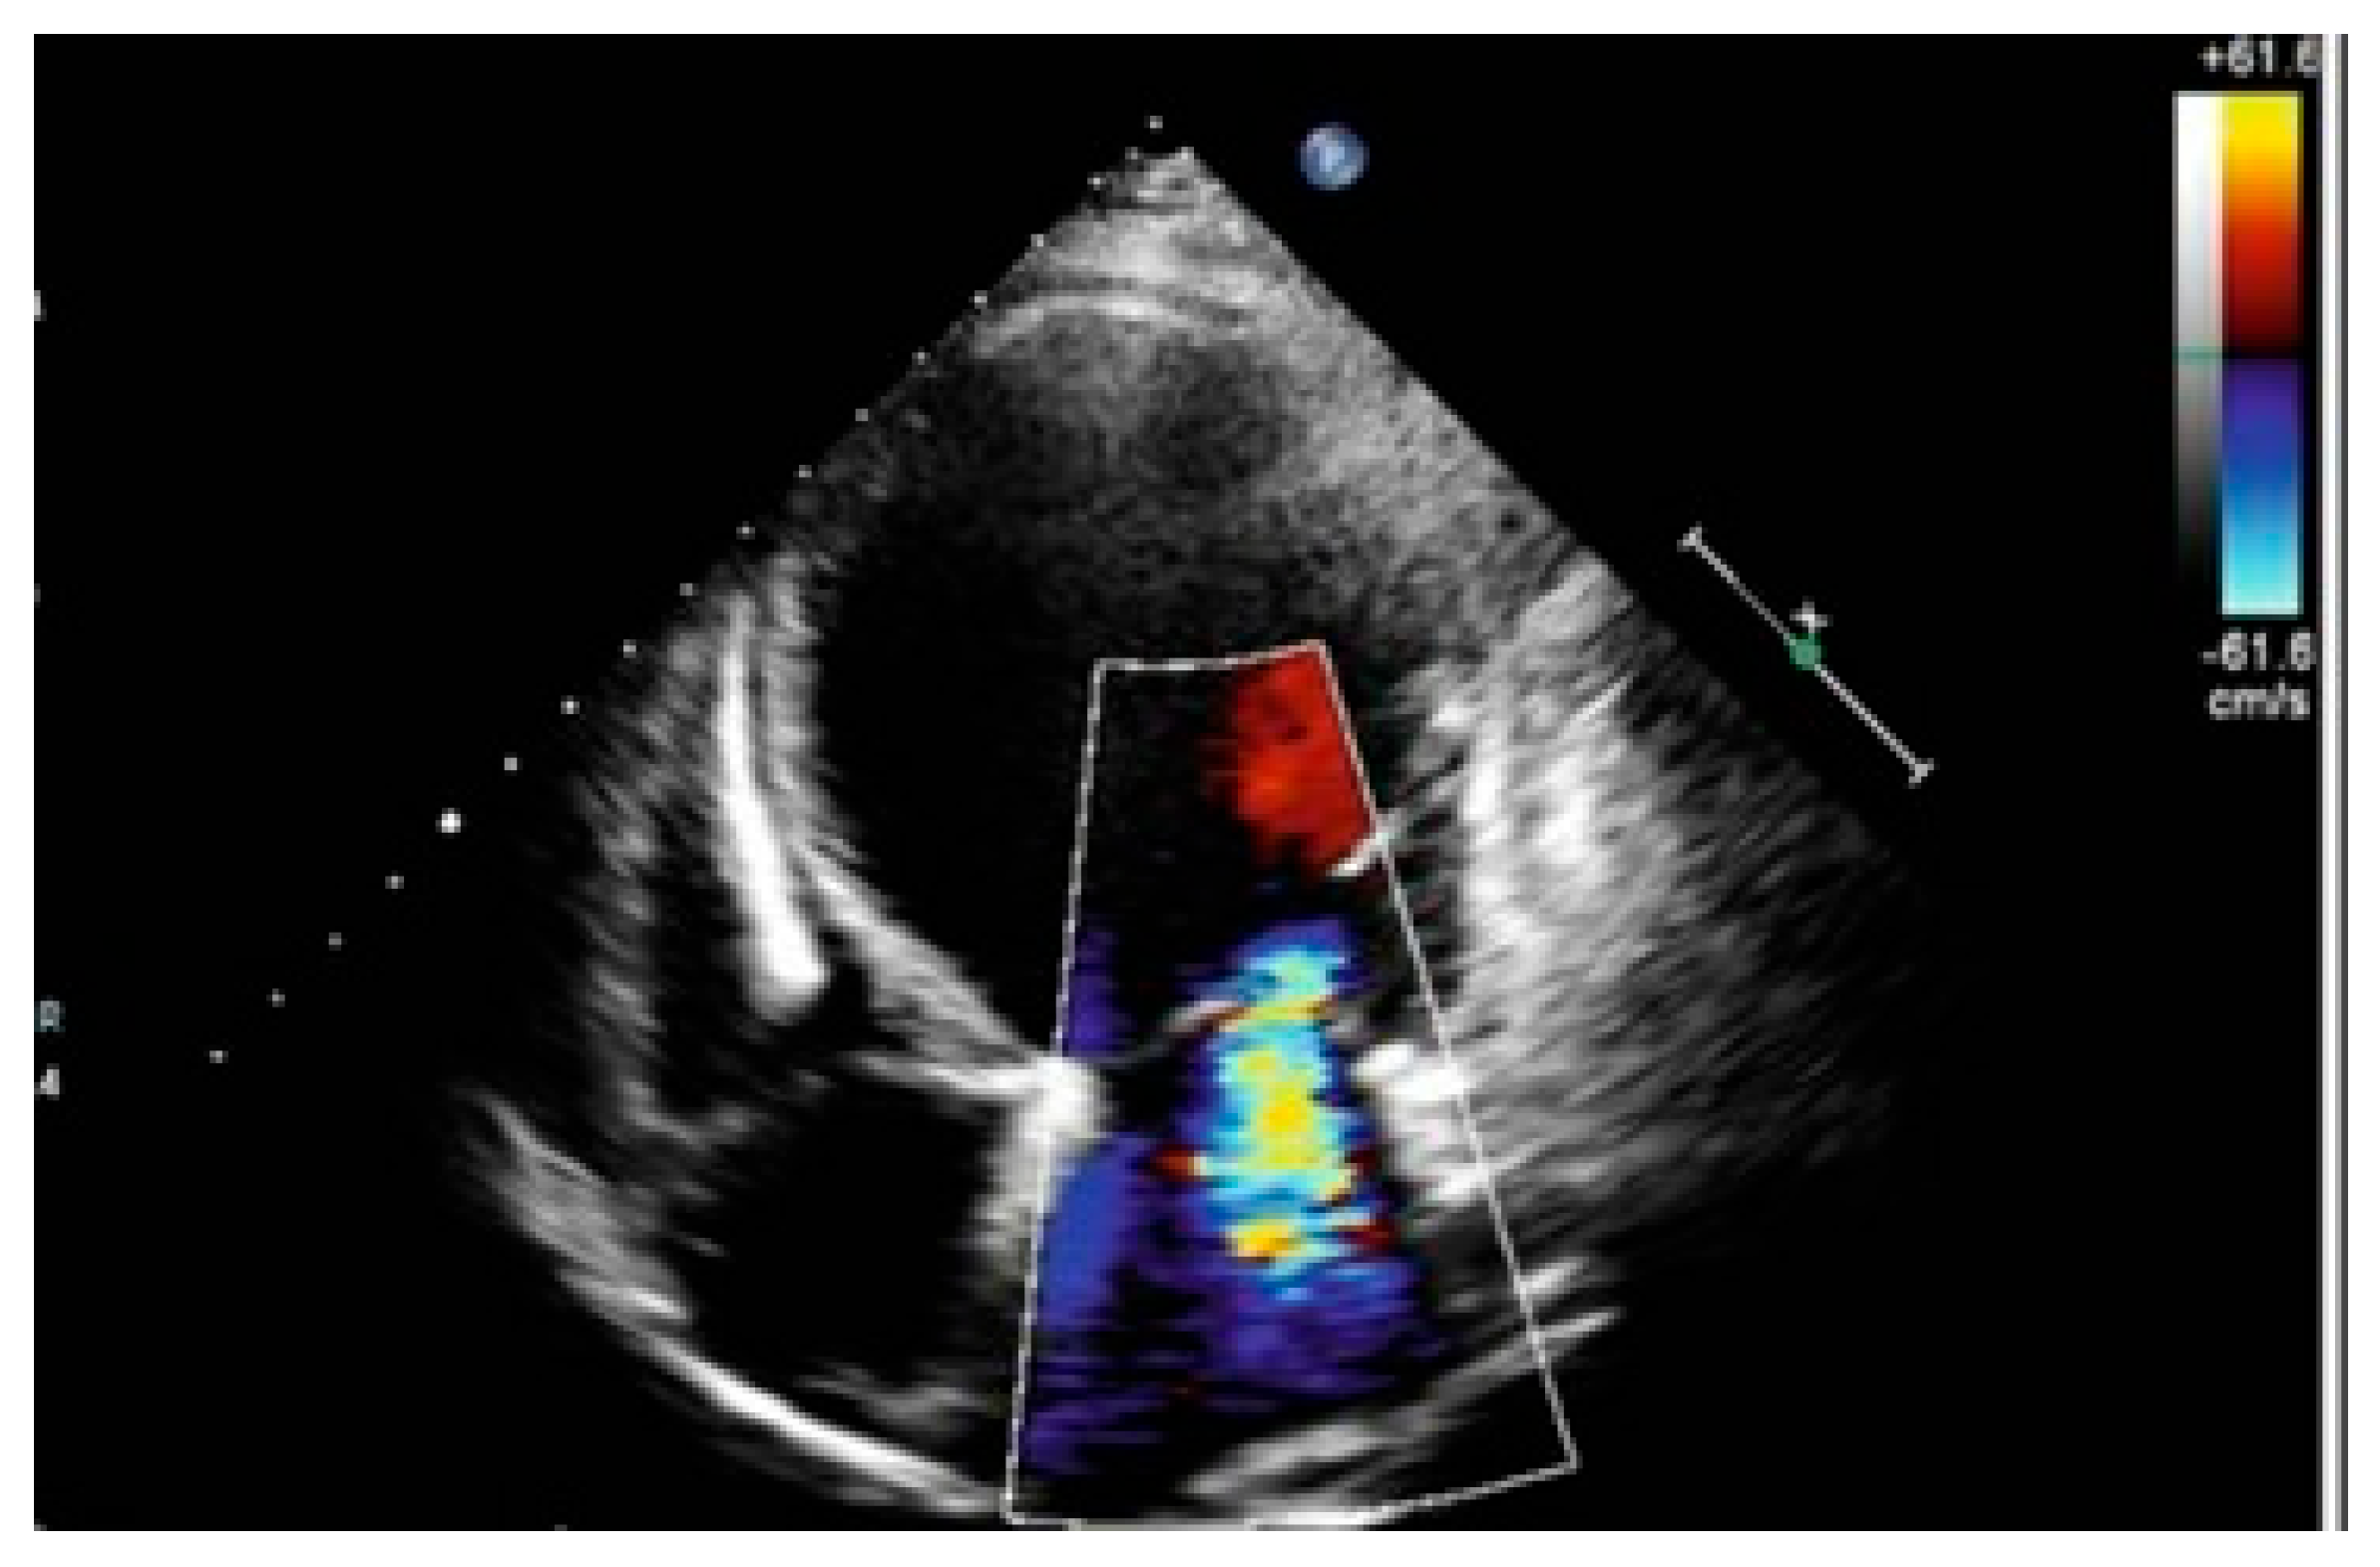

2. Case Presentation